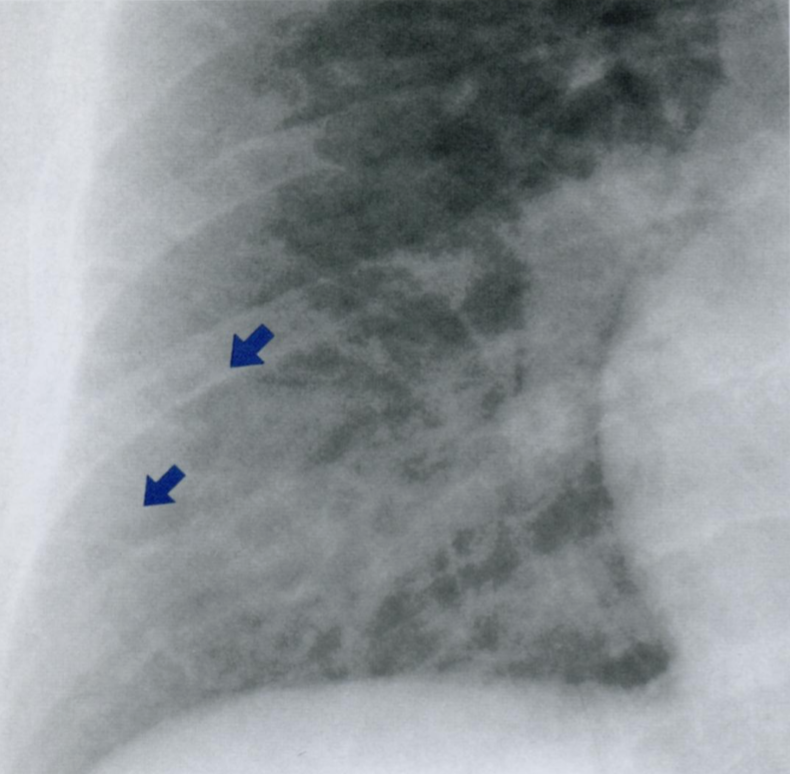

Q

Что отмечено стрелками на снимке?

Что такое линии Кёрли? Какие типы Вы знаете?

Интерстициальные заболевания легких характеризуются ретикулоузловой картиной паутиноподобных затенений из-за наложения отечных междольковых перегородок + мелкоочаговых затенений с четкими границами.

A

Поверхностные лимфатические протоки легких, в даном случае с признаками застоя походу междольковых перегородок.

На снимке становятся видны в виде линий, которые мы называем линиями Керли. В даном случае линии Керли типа В (короткие линейные затенения 1-2 см. в сублевральной области (на периферии полей легких) в нижнем или среднем отделе легких.

Линии Керли типа А более длинные (до 5 см.), идут от корней легких в верхней доле.

Есть карточка с делением легких на отделы (отделы - не доли, а как бы три этажа легочного поля, чтобы более понятно описывать локализацию структур именно на снимке).